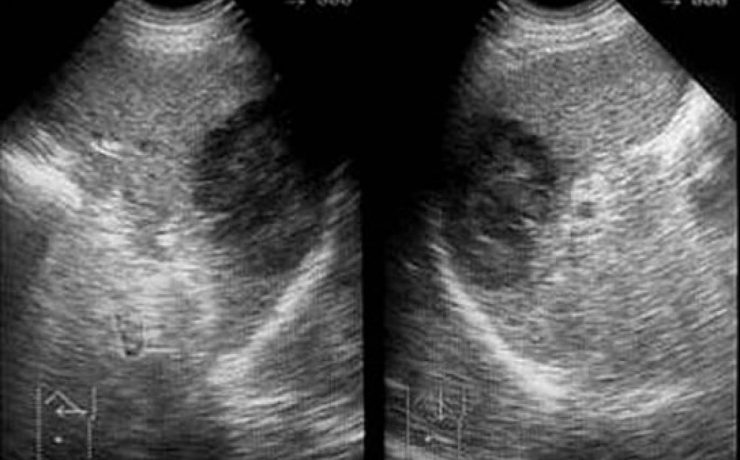

La equinococosis alveolar es causado por el metacestodo Equinococcus multilocularis, en los humanos proliferan en el hígado, induciendo un crecimiento lento progresivo semejante a un tumor. La infección ocurre en todos los continentes, cursa como una infección crónica con estado latente e incluso más de un tercio con detectados incidentalmente,